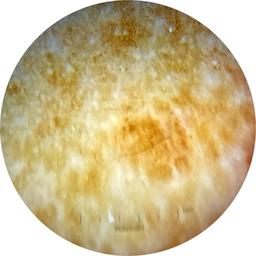

ISIC_5202282

IP_6423627

IL_0565396

anatom_site_1 Upper extremity

anatom_site_general upper extremity

diagnosis_1 Benign

image_type dermoscopic